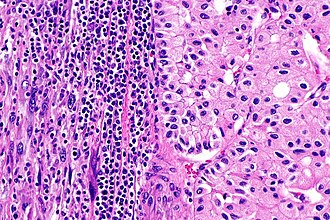

- Sarcomatoid differentiation in renal cell carcinoma -- intermed mag.jpg

RCC with sarc. diff. - intermed. mag. (WC)

- Sarcomatoid differentiation in renal cell carcinoma -- high mag.jpg

RCC with sarc. diff - high mag. (WC)

- Clear cell renal cell carcinoma - 2 -- intermed mag.jpg

CCRCC - intermed. mag. (WC)